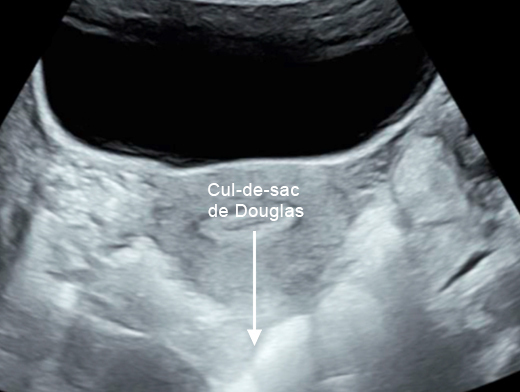

Mme G. est finalement césarisée sous anesthésie générale sans complication. Lors de l’hystérotomie, le liquide amniotique est sanglant avec de nombreux caillots. Les pertes sanguines sont estimées à 1 500 mL. L’équipe d’anesthésie a administré en peropératoire un culot de globules rouges et un plasma frais congelé (PFC), ainsi que de l’acide tranexamique. L’utérus est tonique en fin d’intervention. Au cours de la surveillance en salle de surveillance post-interventionnelle (SSPI), à quatre heures postopératoires, Mme G. a une barre épigastrique résistante aux antalgiques de palier 3. Les constantes sont les suivantes : pression artérielle = 190/110 mmHg ; fréquence cardiaque = 120 bpm ; saturation en oxygène = 99 % en air ambiant. Compte tenu de la tachycardie, vous réalisez une échographie transabdominale dont les images sont les suivantes. Figure 2a (Rodolphe Matias de Sousa, La Revue du Praticien)Figure 2b (Rodolphe Matias de Sousa, La Revue du Praticien)Figure 2c (Rodolphe Matias de Sousa, La Revue du Praticien) Vous décidez d’avancer le prochain bilan biologique et récupérez les résultats suivants : hémoglobine = 8,7 g/dL ; plaquettes = 40 G/L ; TP = 65 % ; TCA = 1,02 ; fibrinogène = 2 g/L ; haptoglobine indosable ; ASAT = 260 UI/L ; ALAT = 240 UI/L.

Concernant l’hématome sous-capsulaire du foie : Tableau 3 (Rodolphe Matias de Sousa, La Revue du Praticien) Concernant l’échographie transabdominale à la recherche d’un hémopéritoine :on regarde deux espaces, le cul-de-sac de Douglas entre l’utérus et le rectum, et l’espace de Morrison entre le foie et le rein. Figure 3a (Rodolphe Matias de Sousa, La Revue du Praticien)Figure 3b (Rodolphe Matias de Sousa, La Revue du Praticien)Figure 3c (Rodolphe Matias de Sousa, La Revue du Praticien) Pour rappel, concernant l’échographie en gynécologie : Figure 4a (Rodolphe Matias de Sousa, La Revue du Praticien)Figure 4b (Rodolphe Matias de Sousa, La Revue du Praticien)Figure 4c (Rodolphe Matias de Sousa, La Revue du Praticien)Figure 4d (Rodolphe Matias de Sousa, La Revue du Praticien)Figure 4e (Rodolphe Matias de Sousa, La Revue du Praticien)Figure 4f (Rodolphe Matias de Sousa, La Revue du Praticien)Figure 4g (Rodolphe Matias de Sousa, La Revue du Praticien)Figure 4h (Rodolphe Matias de Sousa, La Revue du Praticien)Figure 4i (Rodolphe Matias de Sousa, La Revue du Praticien)